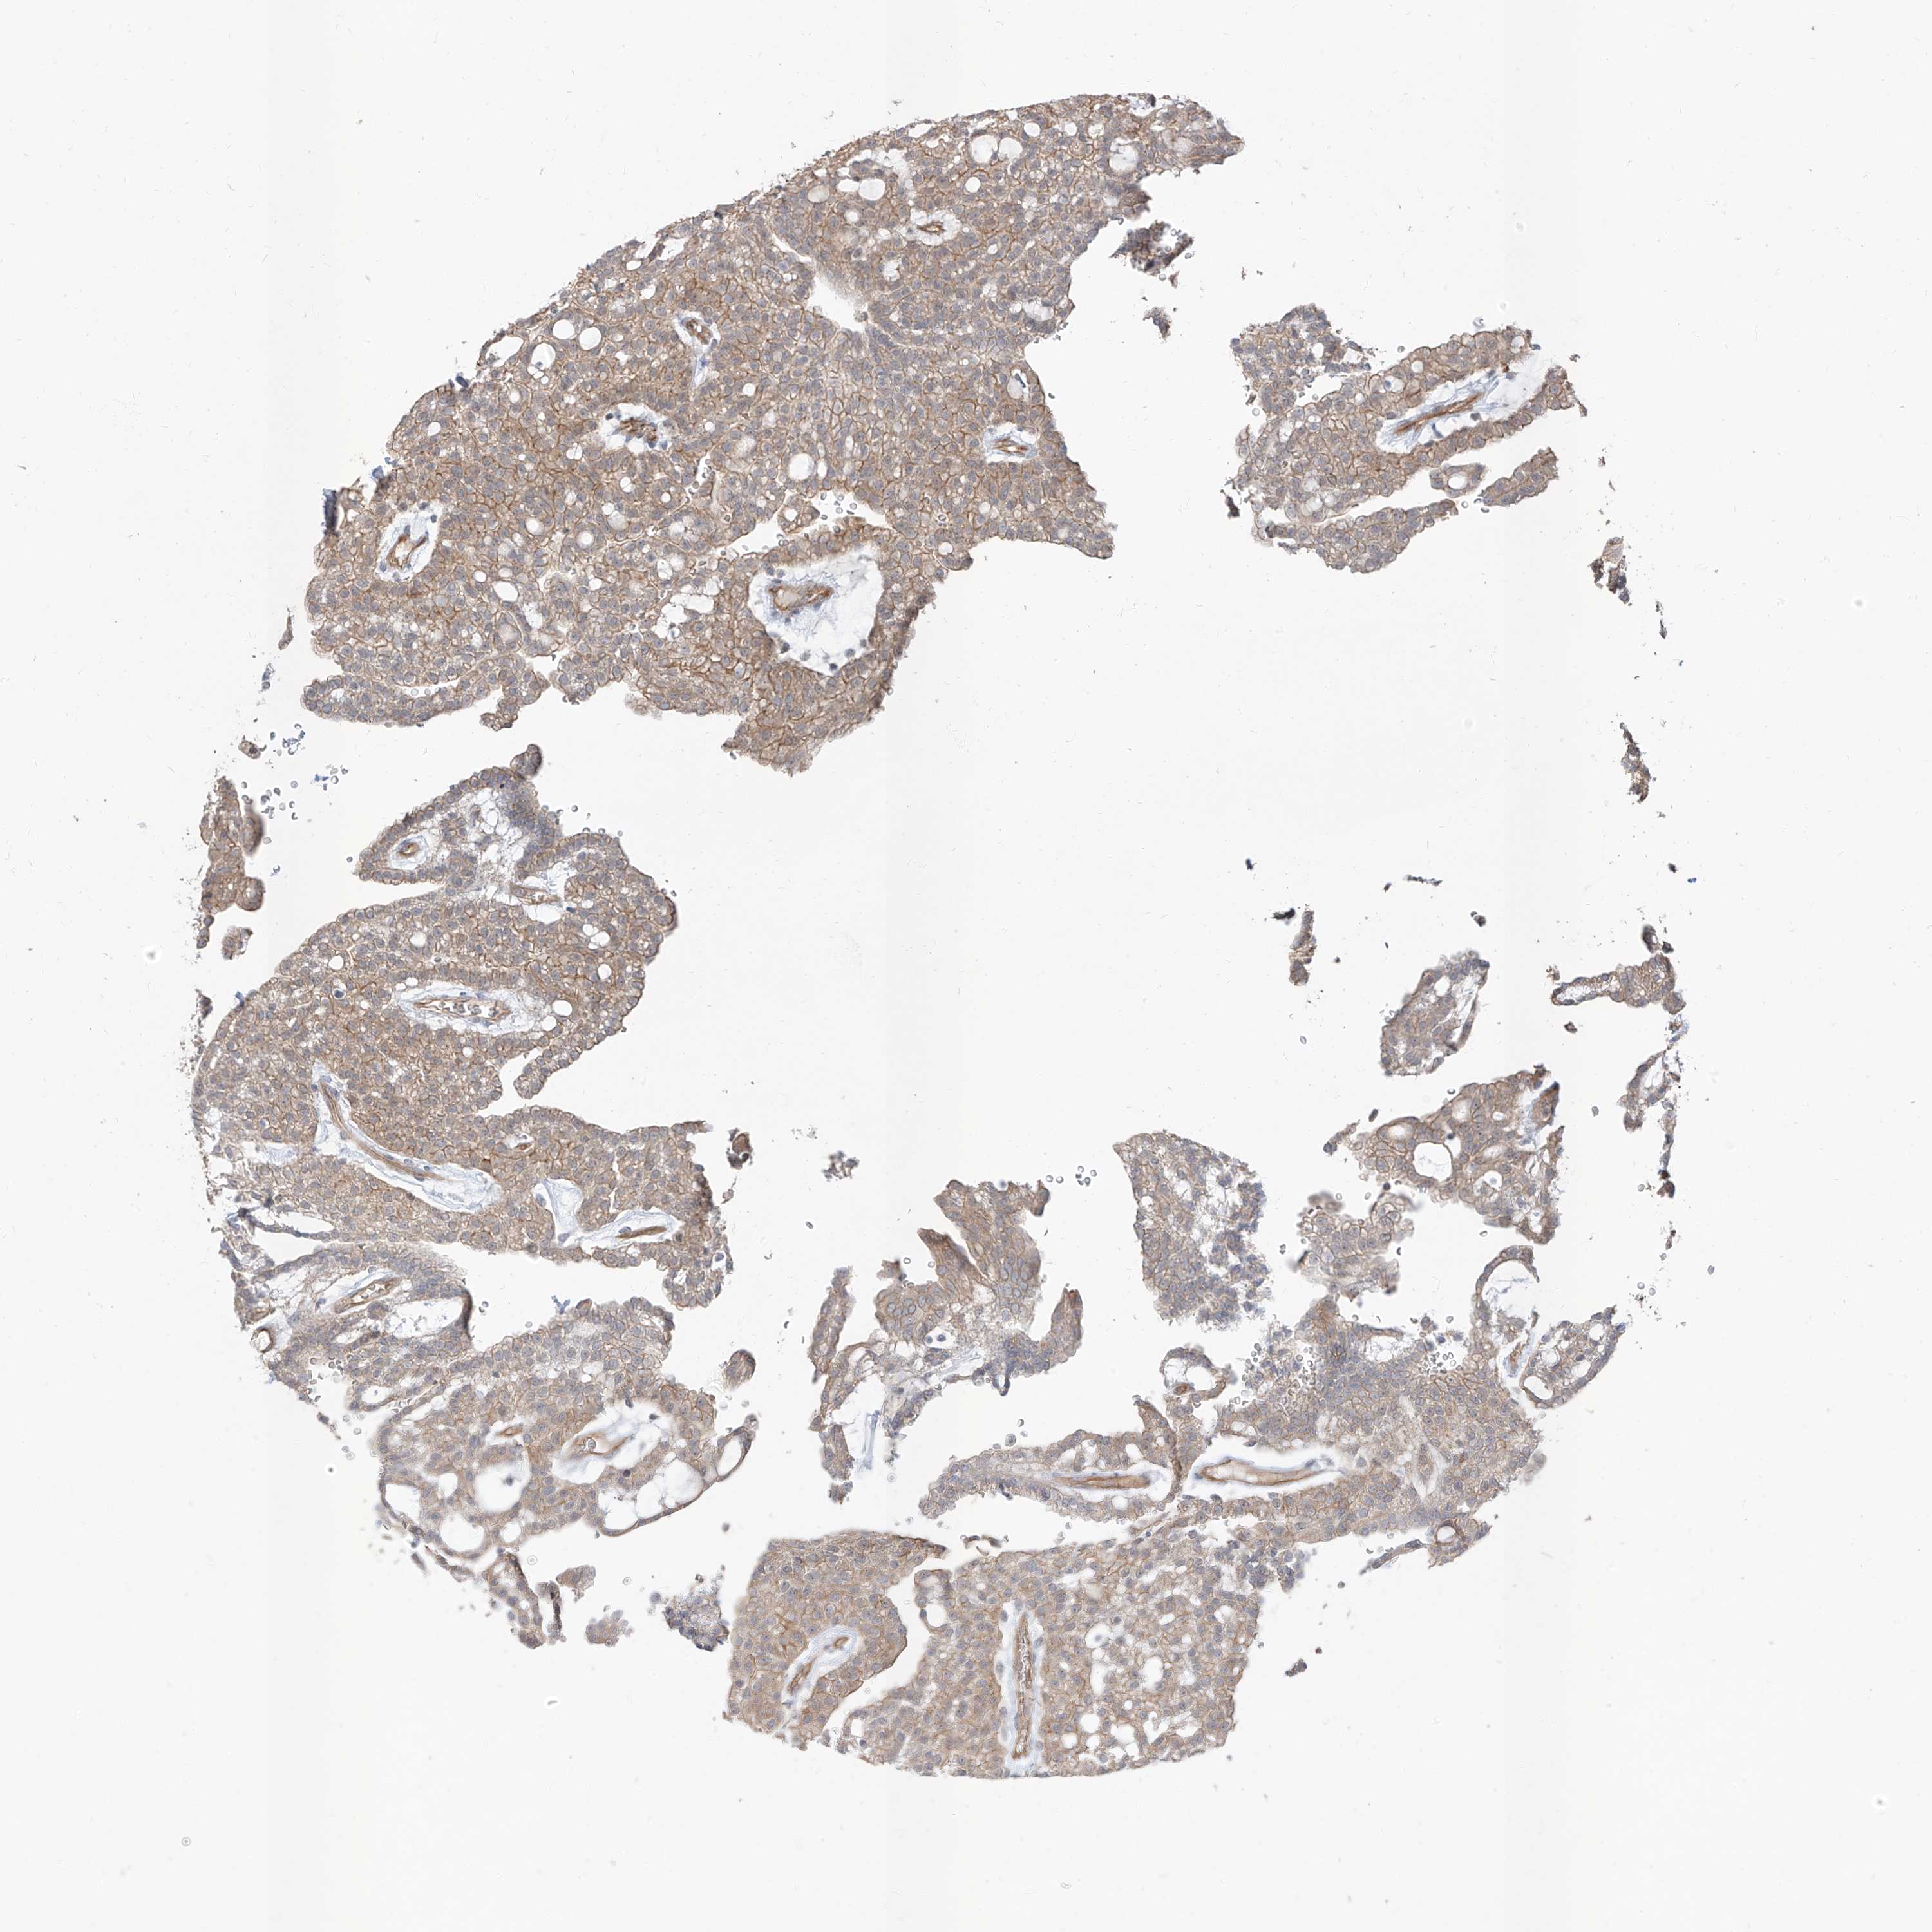

KIDNEY RENAL CLEAR CELL CARCINOMA (VALIDATION) - Interactive survival scatter ploti

The Survival Scatter plot shows the clinical status (i.e. dead or alive) for all individuals in the patient cohort, based on the same data that underlies the corresponding Kaplan-Meier plots. Patients that are alive at last time for follow-up are shown in blue and patients who have died during the study are shown in red.

The x-axis shows the expression levels (FPKM) of the investigated gene in the tumor tissue at the time of diagnosis. The y-axis shows the follow-up time after diagnosis (years). Both axes are complimented with kernel density curves demonstrating the data density over the axes. The top density plot shows the expression levels (FPKM) distribution among dead (red) and alive patients (blue). The right density plot shows the data density of the survived years of dead patients with high and low expression levels respectively, stratified using the cutoff indicated by the vertical dashed line through the Survival Scatter plot. This cutoff is automatically defined based on the FPKM cutoff that minimizes the p-score. The cutoff can be changed by dragging the vertical line or by entering a cutoff value in the square labeled "Current cut-off".

Under the Survival Scatter plot the p-score landscape (black curve; left axis) is shown together with dead median separation (red curve; right axis). Dead median separation is the difference in median mRNA expression between patients who have died with high and low expression, respectively. It is calculated as follows: median FPKM expression of dead patients with high expression - median FPKM expression of dead patients with low expression. This is intended to aid the user in visually exploring custom cutoffs and the associated p-scores and dead median separation.

Individual patient data is displayed and can be filtered by clicking on one or more of the category buttons on the top of the page. Categories describing expression level and patient information include: high, low, alive, dead, female, male and tumor stages. The scale of the x-axis can be toggled between linear and log-scale by clicking on the "x log" button. Mouse-over function shows TCGA ID, patient information and mRNA expression (FPKM) for each patient.

& Survival analysisi

Kaplan-Meier plots summarize results from analysis of correlation between mRNA expression level and patient survival. Patients were divided based on level of expression into one of the two groups "low" (under cut off) or "high" (over cut off). X-axis shows time for survival (years) and y-axis shows the probability of survival, where 1.0 corresponds to 100 percent.

EPHX4 is not prognostic in Kidney Renal Clear Cell Carcinoma (validation)

TCGA RNA samplesi

RNA-seq data is reported as average FPKM (number Fragments Per Kilobase of exon per Million reads), generated by the The Cancer Genome Atlas (TCGA) .

Normal distribution across the dataset is visualized with box plots, shown as median and 25th and 75th percentiles. Points are displayed as outliers if they are above or below 1.5 times the interquartile range. FPKM values of the individual samples are presented next to the box plot.

Average pTPM 1.5

Number of samples 100